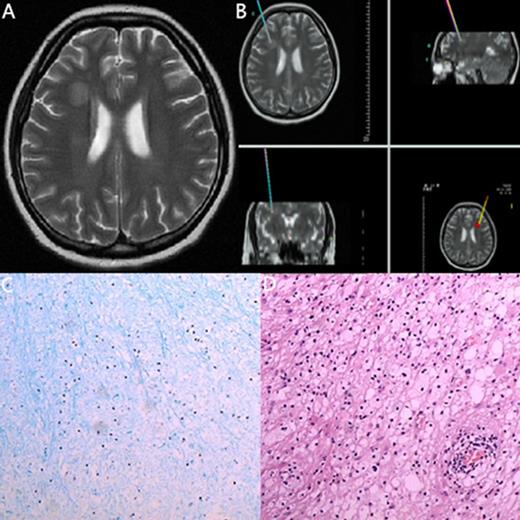

The MRI, biopsy site and pathology of a 23-year-old woman with ALL

| 14 | 23/F | ALL (B cell) | 23/1 mo after allo-ASCT | headache | MRI: The right paracele white matter lesions visible long T1, long T2 signal, the boundary is not clear, edema is not obvious, no enhancemen. | Degenerative disease | Nerve cell degeneration | Improved |